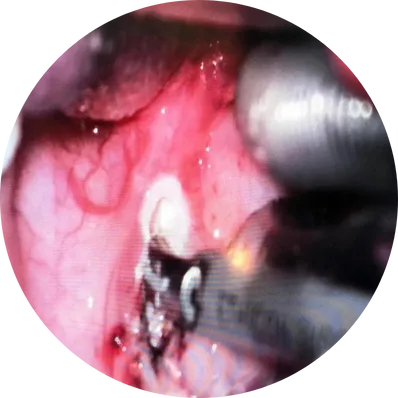

Tonsillectomy Treatment

This is the traditional method where the surgeon removes the tonsils using surgical instruments without heat. It is effective, but may cause more postoperative pain and minor bleeding compared to newer techniques.

Uses electric current to cut tissue and control bleeding simultaneously. This reduces intraoperative bleeding but may cause slightly more pain later due to heat exposure.

A modern technique that uses controlled radiofrequency energy combined with saline to dissolve tonsil tissue at low temperatures. Benefits include minimal pain, less bleeding, and faster recovery. Ideal for children and adults.

Uses ultrasonic energy to cut and coagulate tissue. Results in less bleeding, minimal tissue damage, and smoother healing.

The surgery is done under general anesthesia through the mouth with no external cuts. Healic surgeons use modern techniques like electrocautery or coblation for less pain and minimal bleeding.